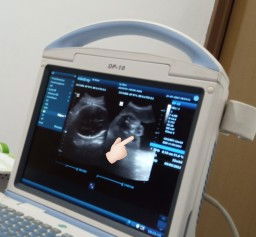

Hi kka² bunda²,, mau tanya dong.. ini hasil USG aku wktu 32 week.. skrg udh 36week. Dr kehamilan 19week sih kt dokternya JK nya memang Laki².. nah, ini hasil USG di 32 week. Apaa ini benar JK nya laki².. (krna ada berupa biji) 😁 ini kehamilan pertama aku. Dan emg mengidamkan Bayi laki² untuk anak pertama. Mohon jawaban nyaa yaa kaka² dan bunda² yang udah berpengalaman..#seriusnanya #bantusharing #ingintahu #firstmom #pleasehelp #firstmom #pleasehelp